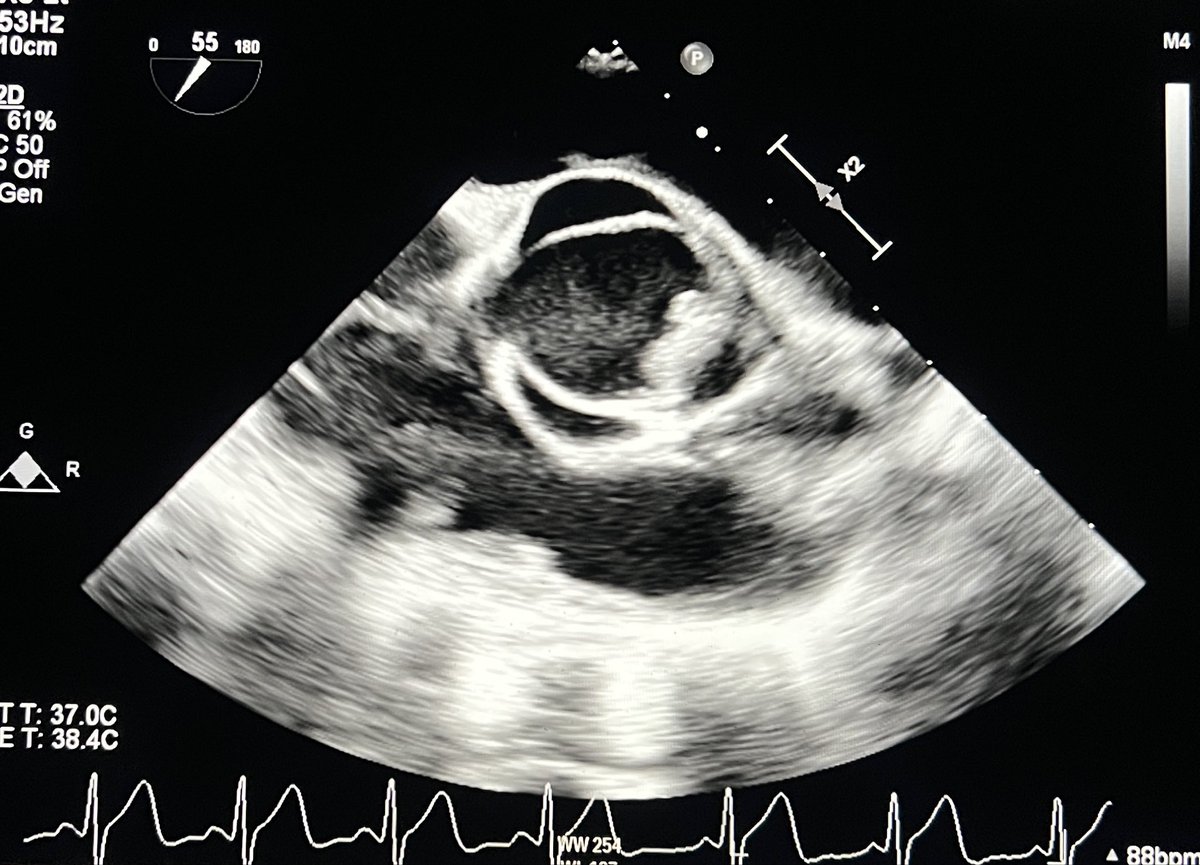

@CASivaram1

Chittur Sivaram MD MACP MACC

8 days

#echofirst ✅ Simple quiz for trainees. Identify the specific location and the nature of the pathology ⬇️ ✅ Follow up post soon @DavidWienerMD @PWengrofskyMD @sudarshanballa @PWesslyMD @DrRajeshG1 @iamritu @bwoody58 @argulian @HeartOTXHeartMD @JohnHenryDean